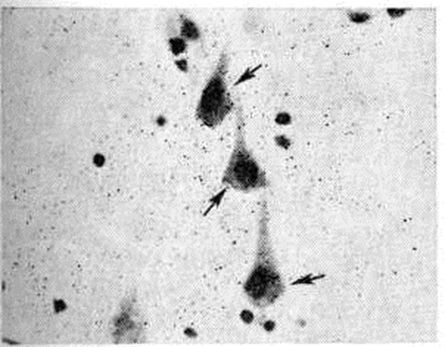

Электронно-микроскопическое исследование коры мозга человека при Инсульт выявляет различные ультраструктурные изменения нейронов, глиальных элементов и капилляров. В ультраструктуре капилляров можно выделить следующие основные патологический изменения: дистрофию стенки капилляра с накоплением в ней лизосомальных включений, липофусциновых гранул, распадом митохондрий, расслоение и вакуолизацию базальной мембраны (рисунок 18). Кроме того, отмечается разрастание и гиперплазия эндотелия. Ультраструктурные повреждения капиллярной стенки сопровождаются разнообразными изменениями из просвета. Обнаруживается ряд изменений основных субмикроскопических компонентов нейронов. Наиболее характерны нейроны, изменённые по гиперхромному типу (рисунок 19), что сочетается с пикнозом ядра, разрушением митохондрий, деструкцией гранулярного и агранулярного ретикулума, наличием большого числа вакуолей и лизосомальных включений, и нейроны с явлениями хроматолиза (рисунок 20), который сопровождается исчезновением цитоплазматических включений, растворением мембранных структур, образованием вместо цистерн ретикулума групп дискретных пузырьков, отсутствием рибосом, набуханием митохондрий, появлением вакуолей. Изменение ультраструктуры капилляров и нейронов сопровождается отёком астроцитарных отростков, скоплением тел глиальных клеток вокруг патологически изменённых элементов. В области расположения патологически изменённого капилляра наблюдаются клетки-тени (клетки в состоянии кариоцитолиза). Прослеживается зависимость изменений элементов одной цепи: нейрон — капилляр — глия.